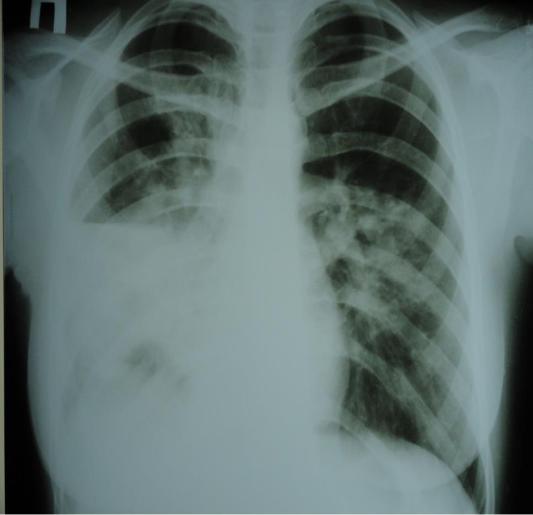

1.Предположите наиболее вероятный диагноз.

2.Обоснуйте поставленный Вами диагноз.

3.Составьте и обоснуйте план дополнительного обследования пациента.

4.Какова тактика лечения данного пациента, назовите препараты «стартовой» терапии и препараты резерва?

5.Какова тактика диспансерного наблюдения пациента после выписка из стационара?